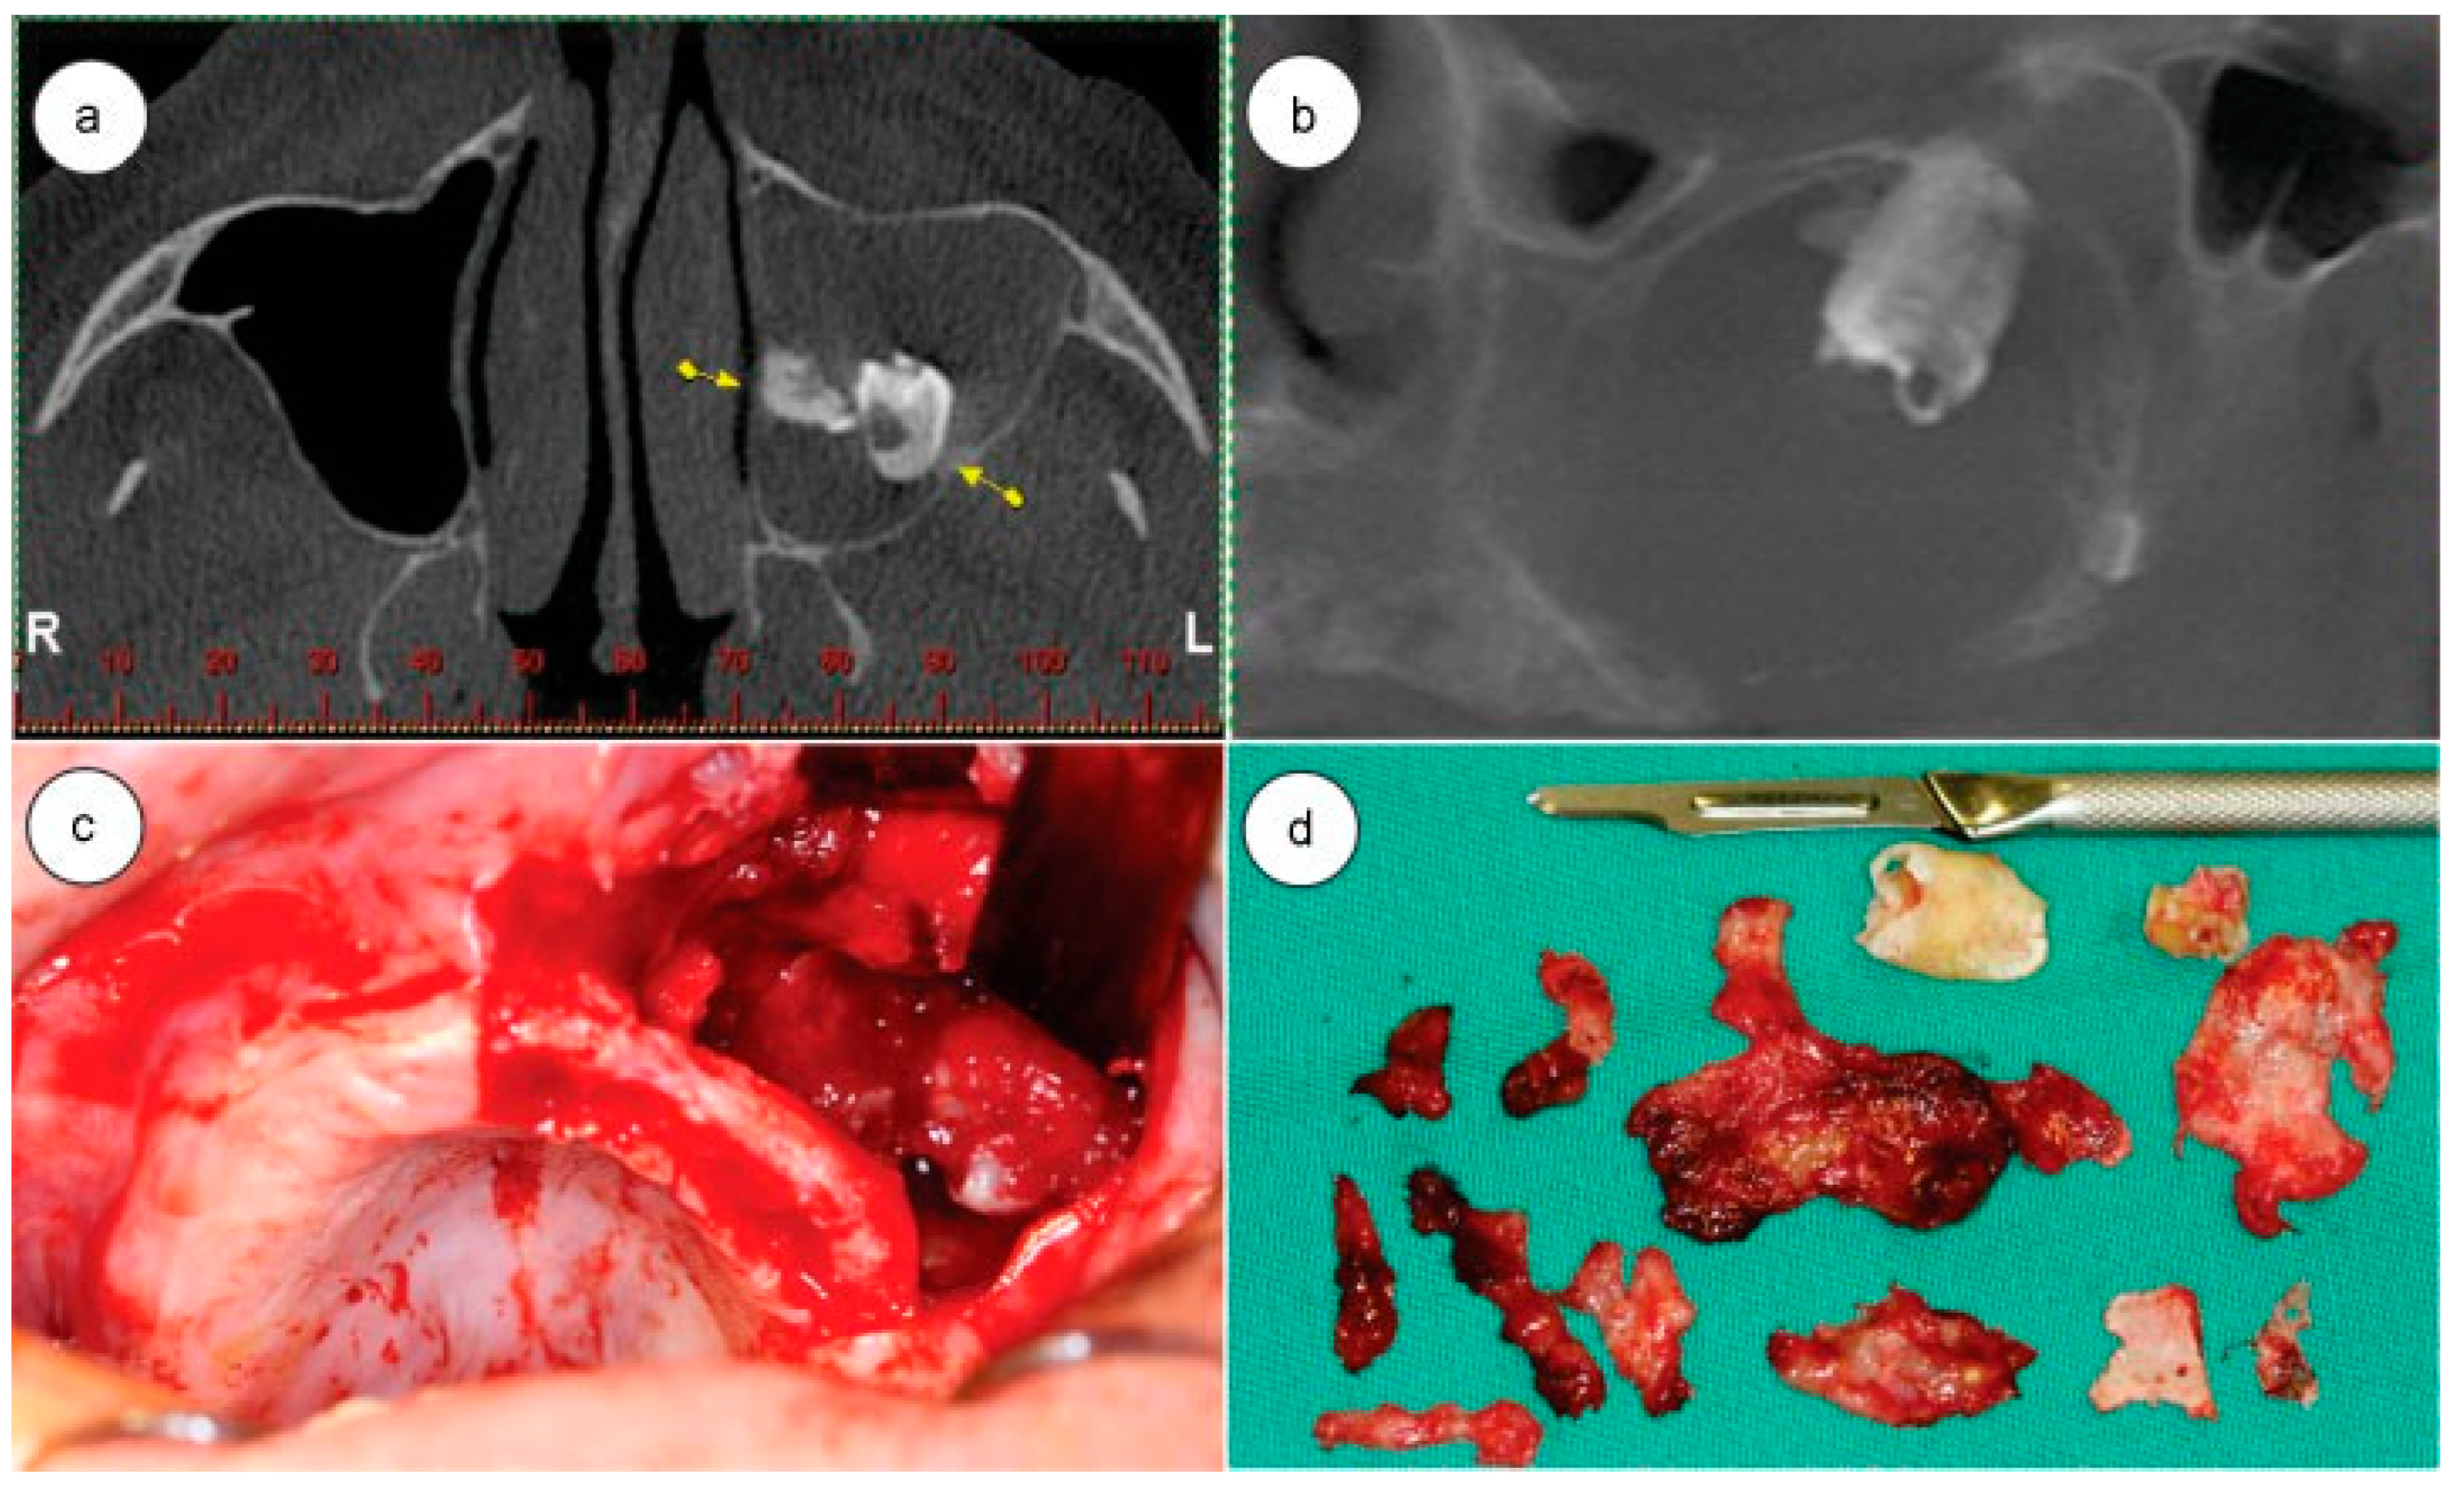

The patient was treated with 875 mg amoxicillin + 125 mg Clavulanate Potassium 1 capsule every 12 hours for 14 days, 1 tablet 100 mg Nimesulide every 12 hours for 4 days, and 1 tablet 750 mg paracetamol every 6 hours in case of pain or fever. After 10 days, the suture was removed, upon which a tiny buccosinusal communication was noted. We opted to wait for a better cicatrization of the area to confirm the clinical picture and eventually perform reconstructive surgery. A CT scan was performed in the immediate postoperative period, in which the complete removal of ectopic structures and the preservation of the maxillary roof sinus and orbital floor could be observed (Figure 2a).

Within 2 weeks after surgery, the patient showed an improvement with respect to respiration and phonation. Clinical examination showed a buccosinusal communication, and after certifying that the maxillary sinus was healthy through its irrigation with 0.9% saline, the communication was closed with the combination of a marginal flap with a vestibular flap performed under local anesthesia (Figure 2b,c).

After a 3-year postoperative follow-up period, the patient has not shown any sinusitis, buccosinusal communication, diplopia, limitation of ocular movements, or any other complaints. The patient is still being followed up (Figure 2d).

Figure 1. (a) Computed tomography (CT) axial slice, arrows are showing the teeth in maxillary sinus; (b) CT coronal slice showing the teeth in maxillary sinus roof; (c) surgical approach showing the tooth; (d) teeth and removed tissue.

Figure 2. (a) Postoperative computed tomography coronal slice showing the healing sinus; (b) postoperative oroantral communication; (c) oroantral communication closure surgery; (d) postoperative 3 years follow-up.